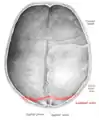

Lambdoid suture

The lambdoid suture (or lambdoidal suture) is a dense, fibrous connective tissue joint on the posterior aspect of the skull that connects the parietal bones with the occipital bone. It is continuous with the occipitomastoid suture.

The lambdoid suture is between the paired parietal bones and the occipital bone of the skull. It runs from the asterion on each side.